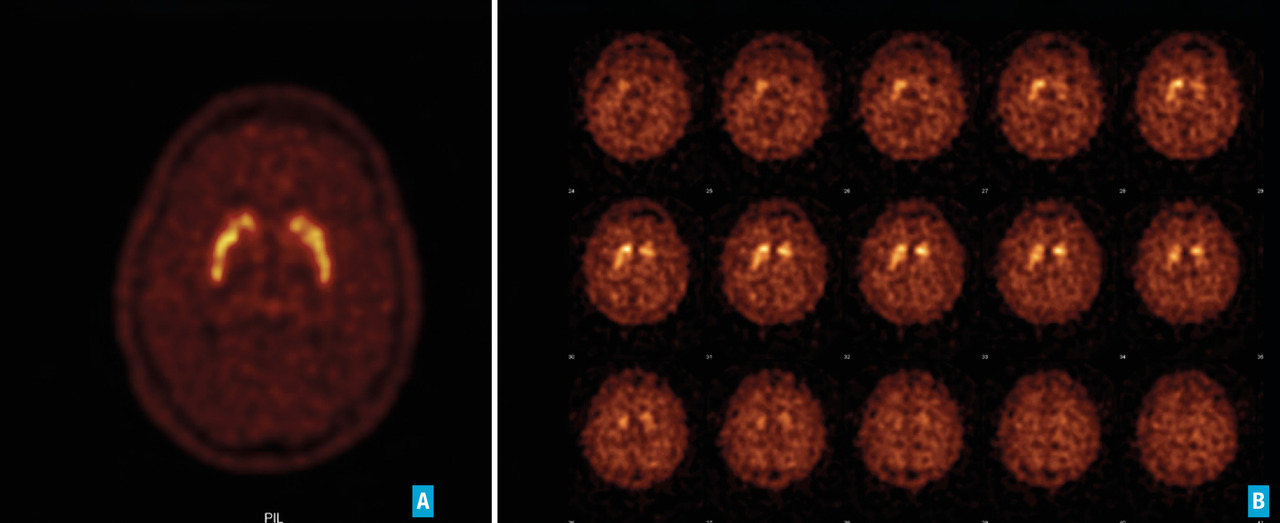

L’imagerie cérébrale morphologique et fonctionnelle (fig. 2-7) occupe une place prépondérante dans la recherche d’arguments en faveur d’une pathologie neurométabolique (maladie de Wilson chez les sujets jeunes), de lésions vasculaires ou d’une hydrocéphalie à pression normale. L’IRM cérébrale permet également de mettre en évidence des anomalies évocatrices de certains syndromes parkinsoniens dégénératifs.

Les progrès de l’imagerie fonctionnelle apportent une aide au diagnostic.